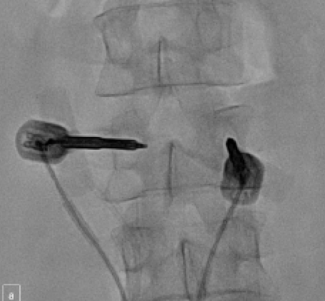

Abstract Painful spinal metastases are a common occurrence among patients with advanced disease. Radiation therapy (RT) is the primary treatment modality for patients with painful spinal metastases, but treatment can be limited by the...